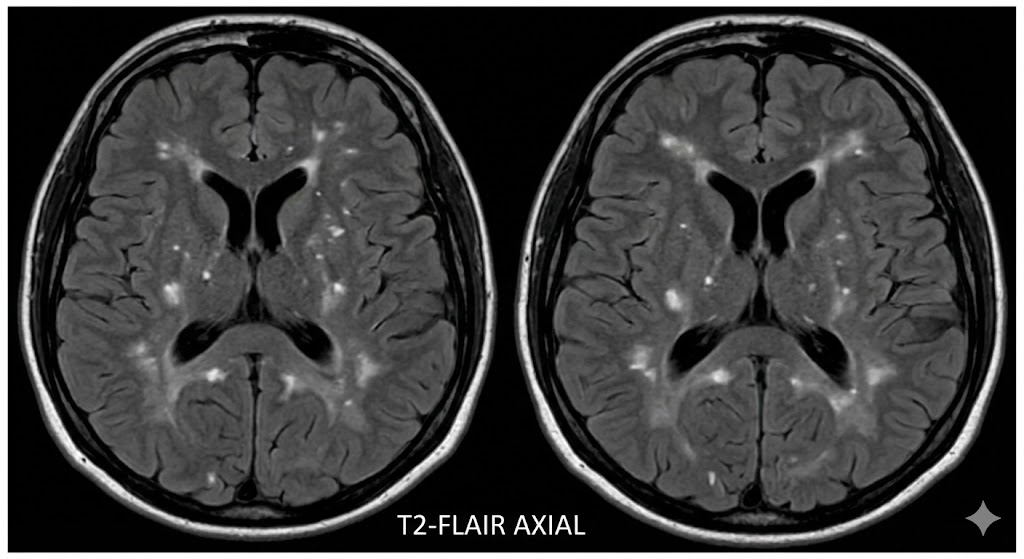

If clinical radiology AI software were overtrained trained on the works of Shakespeare, including his play ‘A Comedy of Errors’, the radiological report on an older person with mild memory impairment and early-stage cerebral microvascular disease as detected by ‘white flecks‘ might read as follows along with the included dietary advice and misquotations 🙂

For scattered round, like stars in darkest night,

Are “white flecks”** glowing with a signal bright.

These “pale distemperatures” of subtle kind,

Have “broke the pale” and clouded up the mind

** “white flecks” is a quotation from my text prompt. To quote Google Gemini: “White flecks” on an MRI scan, medically referred to as white matter hyperintensities (WMH), appear as bright-white spots or areas on specific MRI sequences, particularly T2-weighted and FLAIR images. These images visually represent the damage or changes in the brain’s white matter caused by cerebral microvascular disease.